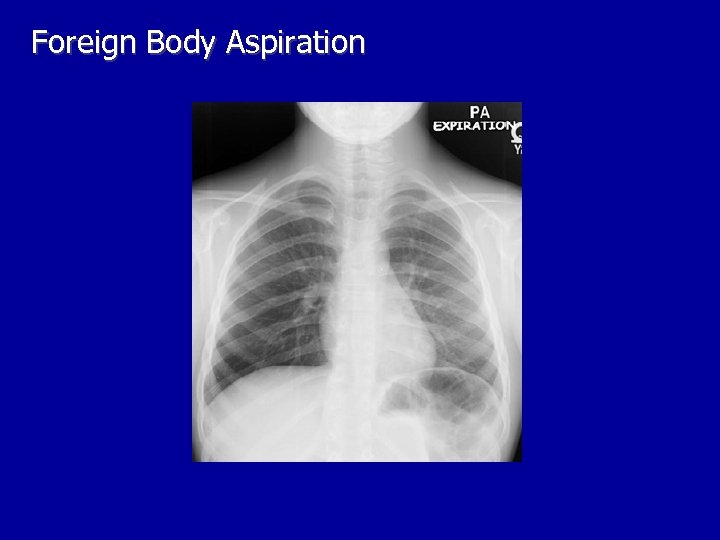

Other Laboratory Findings in ARF CXR Abnormalities Complete Blood Count (look at WBC and Hgb, which may suggest chronic hypoxia) Electrolyte Abnormalities (look at bicarbonate)

Foreign Body Aspiration

Right Lung Atelectasis